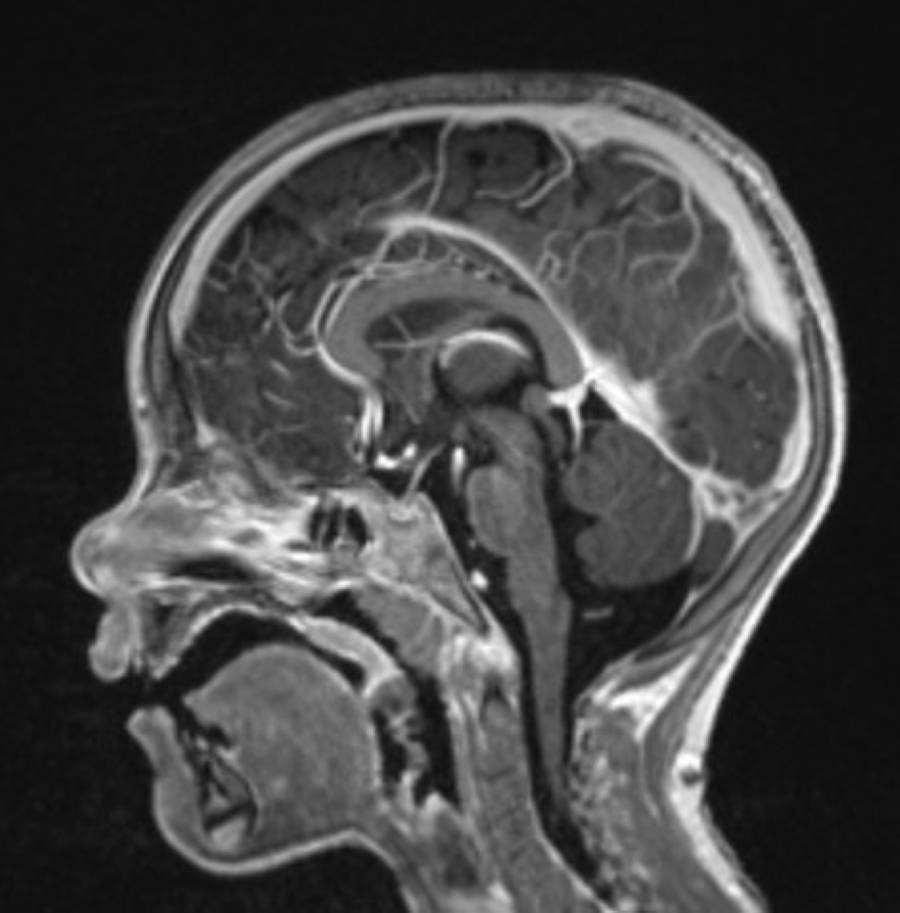

Eine Magnetresonanztomographie, kurz MRT, auch Kernspintomographie genannt, ist ein bildgebendes Verfahren in der Medizin, das ohne schädliche Strahlung auskommt und völlig schmerzfrei ist. Insbesondere für Kinder und Jugendliche kann die MRT als Diagnoseverfahren genutzt werden, da diese hochauflösende Bilder des Körperinneren ermöglicht, ohne Röntgenstrahlung zu verwenden.

Eine Magnetresonanztomographie, kurz MRT, ist ein medizinisches Bildgebungsverfahren, das MRT-Bilder des Körperinneren erstellt. Bei Kindern wird eine MRT oft eingesetzt, um verschiedene Verletzungen, Krankheiten oder Entwicklungsanomalien zu diagnostizieren oder zu überwachen.

Das MRT-Gerät scannt den Körper Ihres Kindes mithilfe eines starken Magnetfelds. Es entstehen Signale, die durch einen Hochleistungsrechner in Bilder übersetzt werden können. Die entstandenen Schnittbilder werden übereinandergelegt, so erhält man präzise und hochauflösende MRT-Bilder der untersuchten Körperregion Ihres Kindes.

Je nach medizinischer Fragestellung wird eine spezifische Körperregion gescannt. Der Körper kann eingeteilt werden in Kopf und Hals, Thorax (Brust, Lunge, Herz), Abdomen und Becken (Bauchraum, Leber, Niere, Blase u.w.), Rücken (Wirbelsäule) und Extremitäten (Arme, Schulter, Beine, Füße).

Gehirn und NervensystemUnser Gehirn ermöglicht sehr viele Funktionen im Körper. Die MRT-Untersuchung gibt uns einen genauen Blick in das Innere unseres Kopfes.